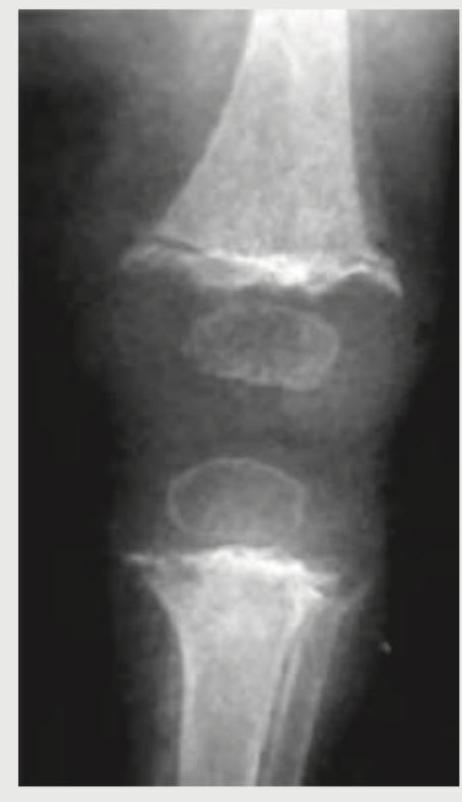

What does the following radiograph show?

Explanation: ***Scurvy*** - The radiograph shows a **dense provisional zone of calcification (white line of Frankel)**, **rarefaction of the metaphysis (Trummerfeld zone)**, and **epiphyseal separation**, which are classic signs of scurvy. - Scurvy results from **vitamin C deficiency**, impairing collagen synthesis crucial for bone matrix formation. *Rickets* - Rickets typically presents with **widened, cupped, and frayed metaphyses** due to impaired mineralization of cartilage in the growth plates. - This image does not show the characteristic widening and fraying of the growth plates seen in rickets. *Osteoid osteoma* - An osteoid osteoma is a **benign bone tumor** characterized by a small radiolucent **nidus** surrounded by dense sclerotic bone. - The findings in the radiograph (metaphyseal changes, epiphyseal separation) are not consistent with osteoid osteoma. *Haemophilia* - Hemophilia causes **recurrent hemarthrosis (bleeding into joints)**, leading to joint destruction, synovial hypertrophy, and subchondral bone cysts. - While it can affect bone health, the specific changes seen in this radiograph (e.g., dense provisional zone of calcification) are not typical of hemophilia.